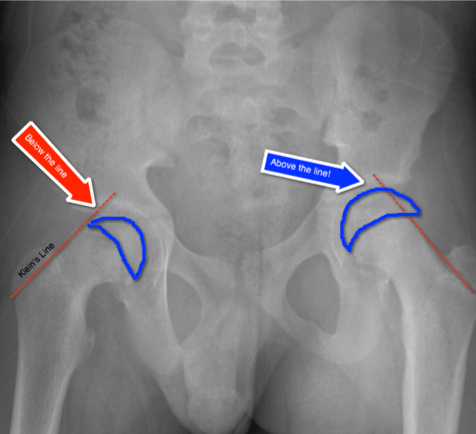

Slipped Capital Femoral Epiphysis Kleins Line

proper-cooking.info

proper-cooking.info

SLIPPED CAPITAL FEMORAL EPIPHYSIS (SCFE) - Www.medicoapps.org

medicoapps.org

medicoapps.org

femoral epiphysis slipped capital scfe line klein head lateral medicoapps